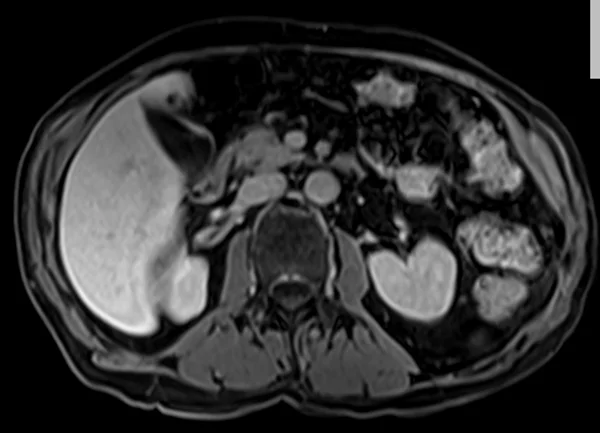

delay 5min 2 - MRI